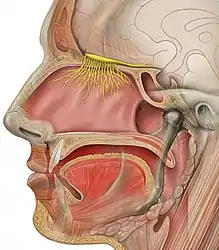

- For months, scientists have observed trends showing older people and men tend to be more vulnerable. Scientists know something about why children tend to have less serious infections from coronavirus -- they have fewer ACE2 receptors in their noses, and these receptors are how coronavirus gets into our cells. But they can't really explain why older people have such a high death rate from coronavirus -- much higher than from the common flu.

- If the (COVID-19) infected (patient) droplets were sneezed at you by a patient and enters your eyes, they will eventually be washed from your eyes to your nose, as both are connected through what is known as a nasolacrimal duct.

SARS-CoV-2, unfortunately, can do both very efficiently. That gives it two places to get a foothold, says Shu-Yuan Xiao, a pathologist at the University of Chicago, Illinois. A neighbour’s cough that sends ten viral particles your way might be enough to start an infection in your throat, but the hair-like cilia found there are likely to do their job and clear the invaders. If the neighbour is closer and coughs 100 particles towards you, the virus might be able get all the way down to the lungs, says Xiao.

These varying capacities might explain why people with COVID-19 have such different experiences. The virus can start in the throat or nose, producing a cough and disrupting taste and smell, and then end there. Or it might work its way down to the lungs and debilitate that organ. How it gets down there, whether it moves cell by cell or somehow gets washed down, is not known, says Stanley Perlman, an immunologist at the University of Iowa in Iowa City who studies coronaviruses. - Clemens-Martin Wendtner, an infectious-disease physician at the Munich Clinic Schwabing in Germany, says it could be a problem with the immune system that lets the virus sneak down into the lungs. Most infected people create neutralizing antibodies that are tailored by the immune system to bind with the virus and block it from entering a cell. But some people seem unable to make them, says Wendtner. That might be why some recover after a week of mild symptoms, whereas others get hit with late-onset lung disease. But the virus can also bypass the throat cells and go straight down into the lungs. Then patients might get pneumonia without the usual mild symptoms such as a cough or low-grade fever that would otherwise come first, says Wendtner. Having these two infection points means that SARS-CoV-2 can mix the transmissibility of the common cold coronaviruses with the lethality of MERS-CoV and SARS-CoV. “It is an unfortunate and dangerous combination of this coronavirus strain,” he says.

- The virus’s ability to infect and actively reproduce in the upper respiratory tract was something of a surprise, given that its close genetic relative, SARS-CoV, lacks that ability. Last month, Wendtner published results8 of experiments in which his team was able to culture virus from the throats of nine people with COVID-19, showing that the virus is actively reproducing and infectious there. That explains a crucial difference between the close relatives. SARS-CoV-2 can shed viral particles from the throat into saliva even before symptoms start, and these can then pass easily from person to person. SARS-CoV was much less effective at making that jump, passing only when symptoms were full-blown, making it easier to contain.